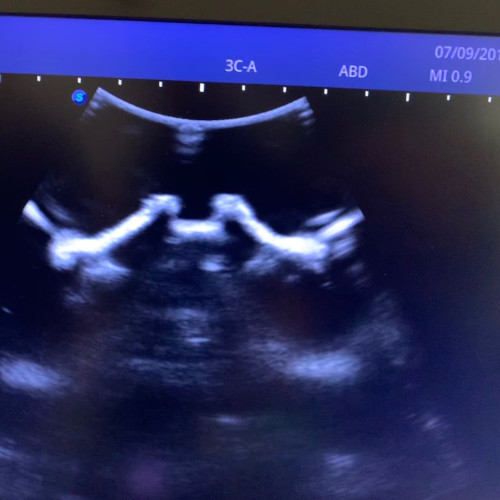

Ultraschall-gezielte Infiltrationsbehandlung – Es handelt sich dabei um eine Ultraschall-gezielte Infiltration ohne Strahlenbelastung. Dadurch können Schmerzen schnell und effektiv behandelt werden. Diese Infiltration kann bei mir in der Ordination durchgeführt werden.

- Ultraschallgezielte Infiltration der Facettengelenke, Nervenwurzeln, ISG und epidurale Flutungen von caudal